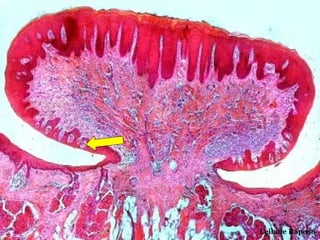

• Qual o corte histológico?

• Que estrutura a seta aponta?

• Qual a coloração utilizada?